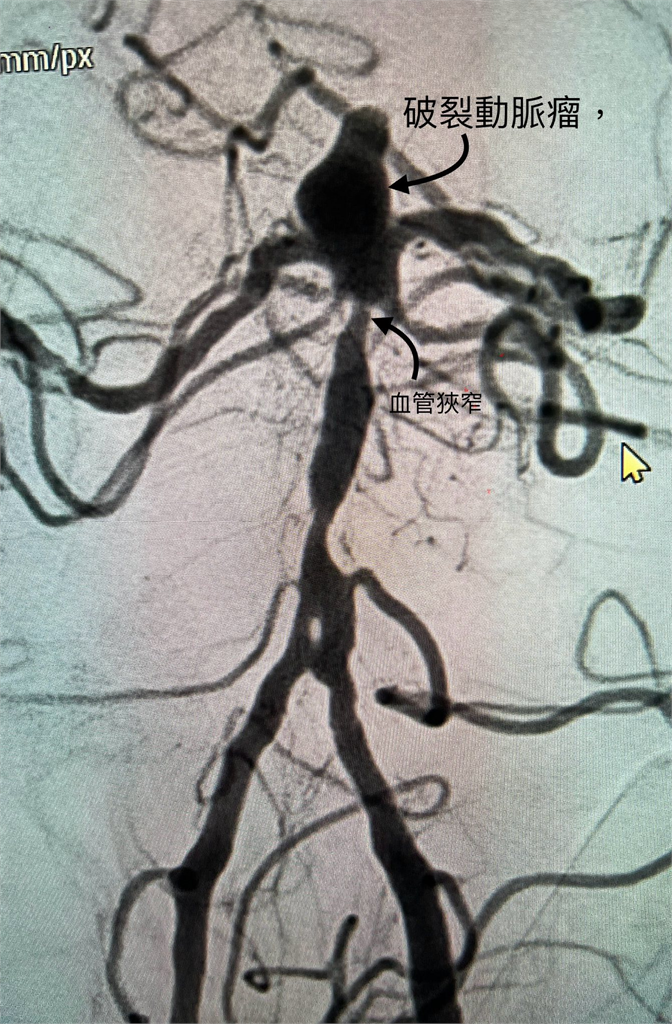

陳啟仁也分享近期急診處理的真實案例,一名患者因動脈瘤破裂送醫,出血衝力甚至穿破第三腦室底板,導致腦室積血與水腦。檢查發現,是一顆7毫米的基底動脈頂端動脈瘤破裂,加上近端血管狹窄,讓血流速度進一步升高,更容易把血管壁沖破。動脈瘤本身並不是腫瘤,而是血管膨出,多與動脈硬化有關,而高血壓、高血脂、糖尿病、抽菸與遺傳都是關鍵因素。陳啟仁再次提醒,天冷時一定要做好保暖,尤其頭部與頸部要戴帽子、圍巾,別讓血管在低溫下承受過大壓力。